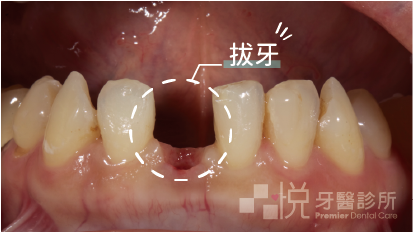

噹噹噹 ~ 沒過多久果然牙齒又出問題了,這次的主角是一顆下顎門牙。和以往不同的事,先前幾次的問題結局都是喜劇,牙齒經過辛苦治療後最終保留下來皆大歡喜,但這次直接悲劇 … 這顆悲慘的下顎門牙咬到鐵筷,X光片上明顯到不行的大裂痕和搖搖欲墜的假牙冠宣布了它提早壽終正寢,只能走向拔牙的大結局。

拔牙了,然後呢?

當然是不能這樣就讓阿婷就這樣回去啊,下顎門牙這麼明顯的一個缺口,沒有一個門面之前阿婷是穩妥妥的黏在我的治療椅上了。

拿出我們在拔牙前就預先準備好的「臨時馬利蘭牙橋」,將兩側牙齒清潔乾淨酸蝕好之後,再將臨時牙橋黏上去就大功告成了。